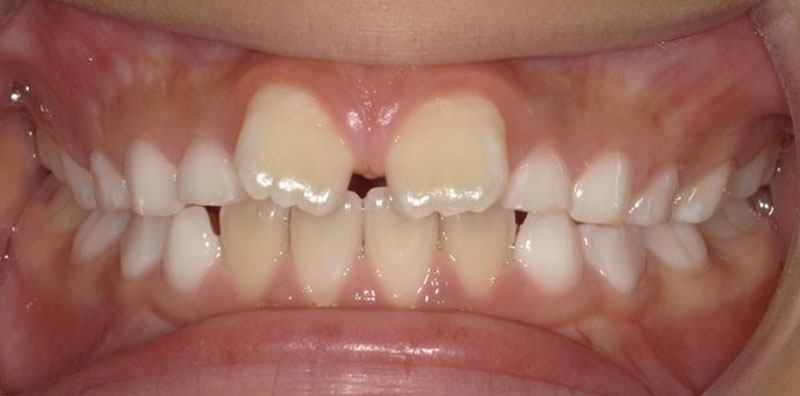

プレオルソによる矯正治療

小児矯正の一つ、プレオルソにて治療をした症例をご紹介します。

プレオルソとは機能的マウスピース矯正治療のひとつでマウスピースを夜寝る前に1時間とそのまま就寝してもらうことで治療していきます。

お口の中は口輪筋を中心に色々な筋肉のバランスと下の筋肉や位置関係で歯並びが変わってきます。

その筋肉をバランスよく鍛え、悪い癖などをとるのがこの装置です。

骨格的な問題がなければ筋肉のバランスを整えることである程度は歯並びが良い状態になります。

矯正しなくても歯並びが綺麗な人はこの状態に近いです。

装置を入れるだけでなく、効果的なお口の体操などのトレーニングも併用していく必要はあります。

治療期間は個人差がありますが早いと3ヶ月ほどで効果が見られるケースもあります。

| 患者様 | 8歳男性 |

| 主訴 | 前歯が開いているのと出ているのが気になる |

| 治療装置 | プレオルソ |

| 治療費 | 11万円(税込) |

| 治療期間 | 6ヶ月経過時 |

| 総治療期間 | 永久歯に全て生え変わるまで |